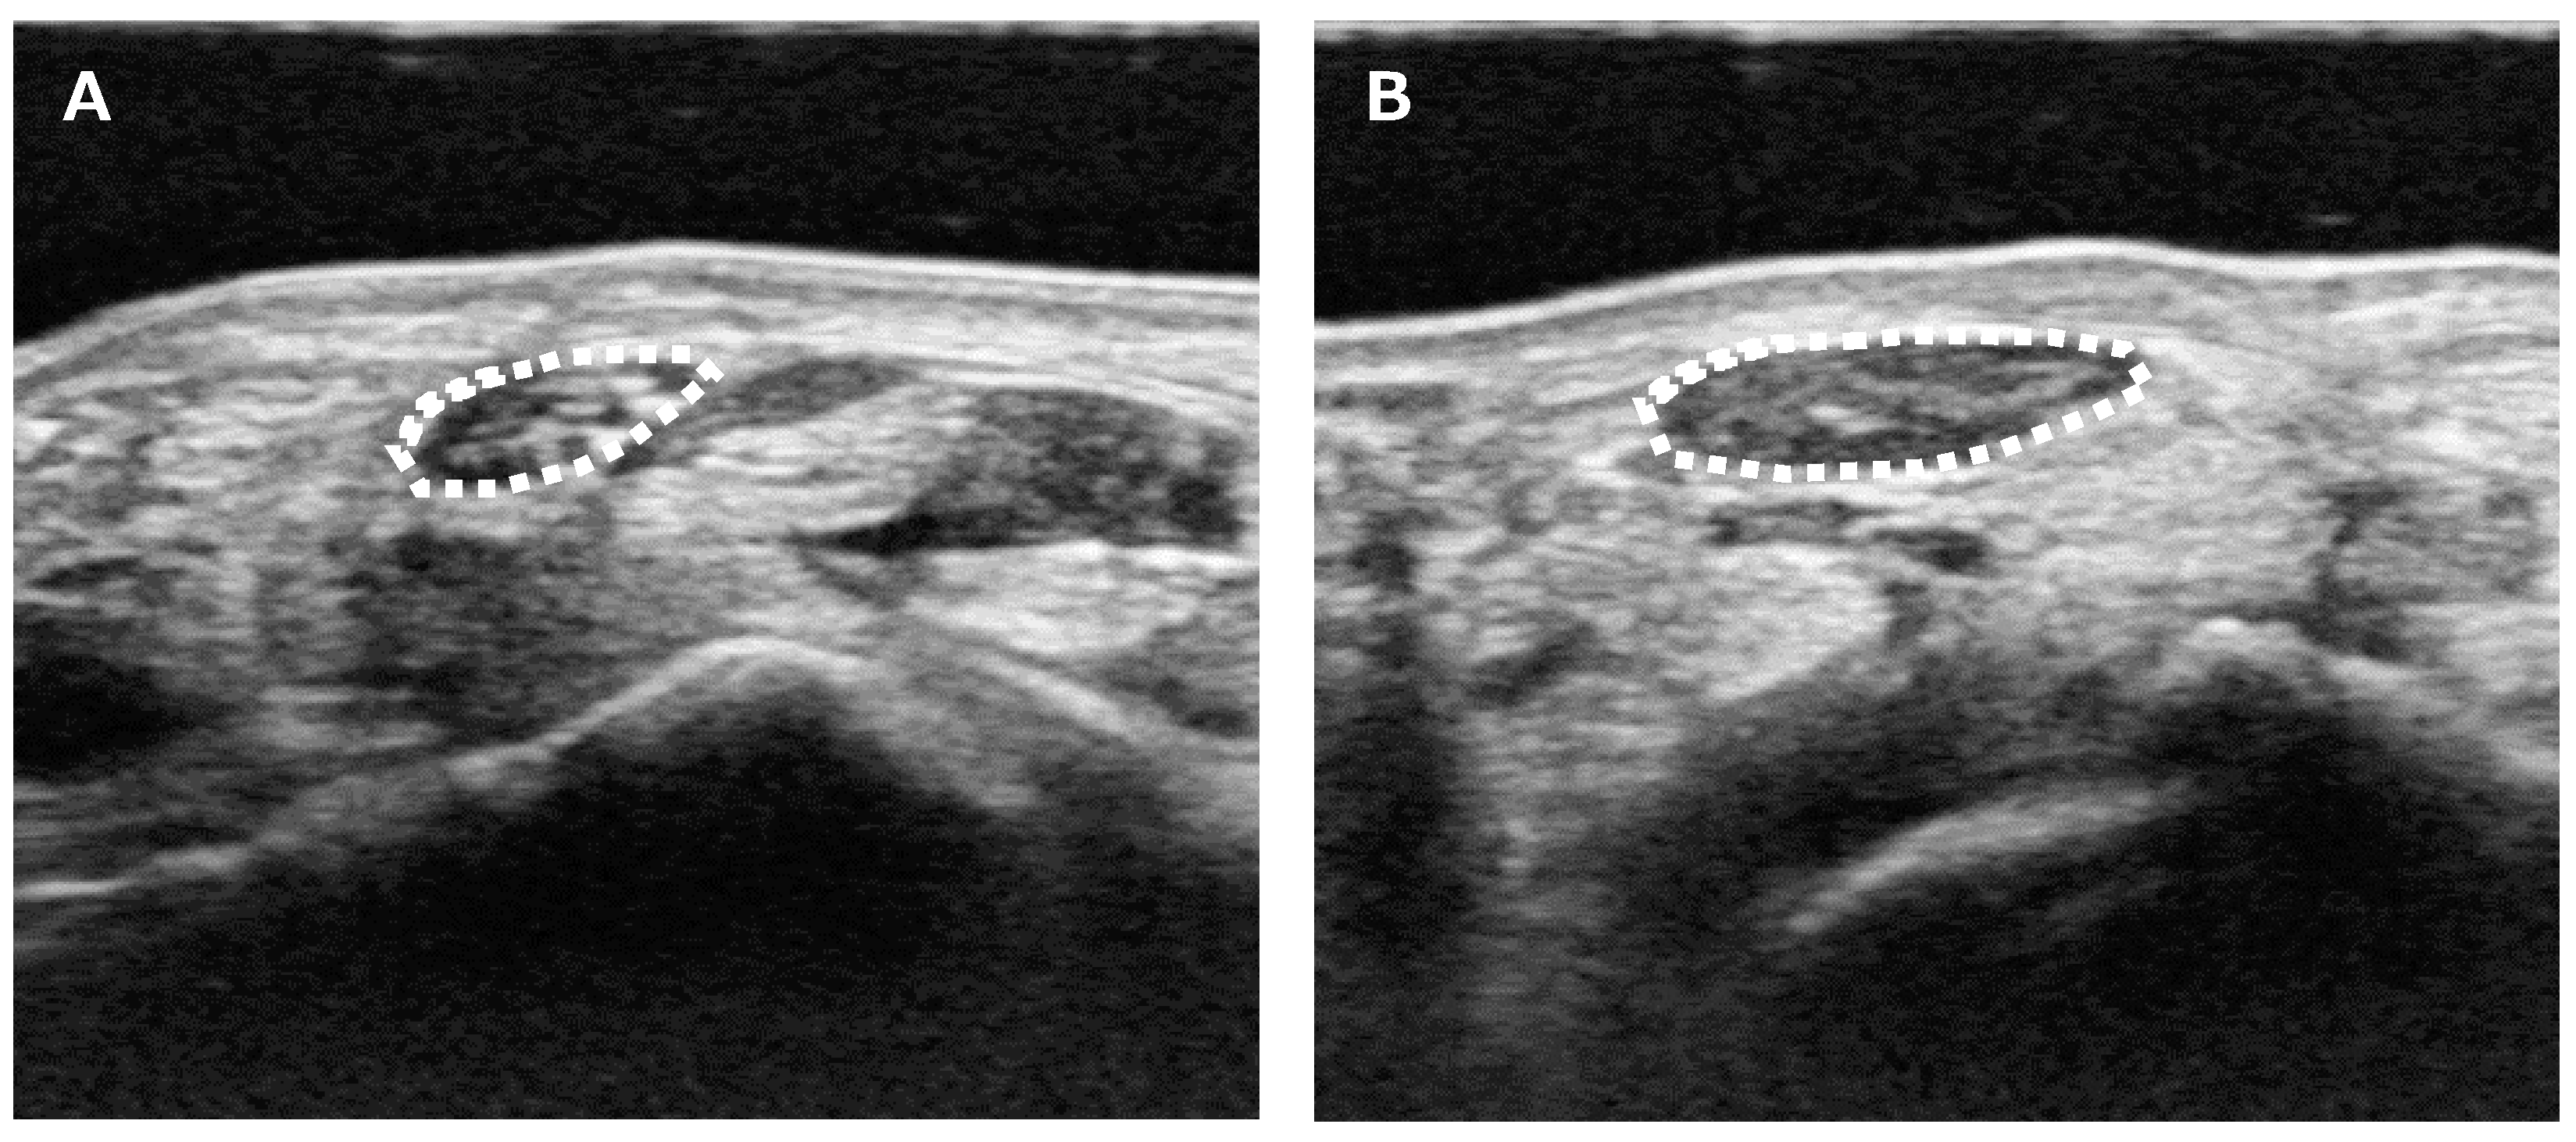

Median nerve CSA was measured using the following method: US was routinely performed on patients with suspected CTS to differentiate abnormalities around the CT. During the diagnostic process, median nerve CSA was measured at the wrist crease level (Figure 1). Each patient was asked to sit and place their forearm on the table with the palmar side up. An ultrasound scanner (Hi Vision Avius; Hitachi Aloka Medical, Ltd., Tokyo, Japan) equipped with a linear array transducer was set to a depth of 20 mm. The frequency of the transducer was 15 MHz. Cross-sectional ultrasonographic images of the CS were analyzed using ImageJ Software (National Institutes of Health, Bethesda, MD, USA). The median nerve was outlined, and its area was calculated. US was performed by a single hand surgeon (YY) who is certified as a specialist and instructor by the Japanese Society of Surgery of the Hand.

Figure 1.

Ultrasound measurement of the median nerve CSA. (A) Unaffected side. (B) Affected side. CSA was measured as the only parameter for the image analysis. Median nerve CSA was measured at the wrist crease level. The median nerve was outlined (white dotted line), and its area was calculated.